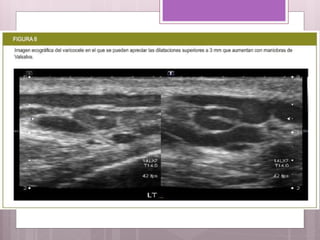

• #13 Ecografia: Es el método más usado pero no proporciona una evaluación cuantitativa. ( FIGURA 8 )

Los grados devaricocele en función del tiempo de reflujo son :  Grado 1: Reflujo inferior a los 3 segundos durante la maniobra de Valsalva.  Grado 2: Reflujo entre los 3 y 5 segundos.  Grado 3: Reflujo por encima de los 5 segundos.  Los grados de varicocele con respecto al calibre de las venas son:  Grado I: Calibres máximos entre 2 y 4 mm.  Grado II: Calibres máximos entre 4 y 5 mm.  Grado III: Calibre por encima de 5 mm.